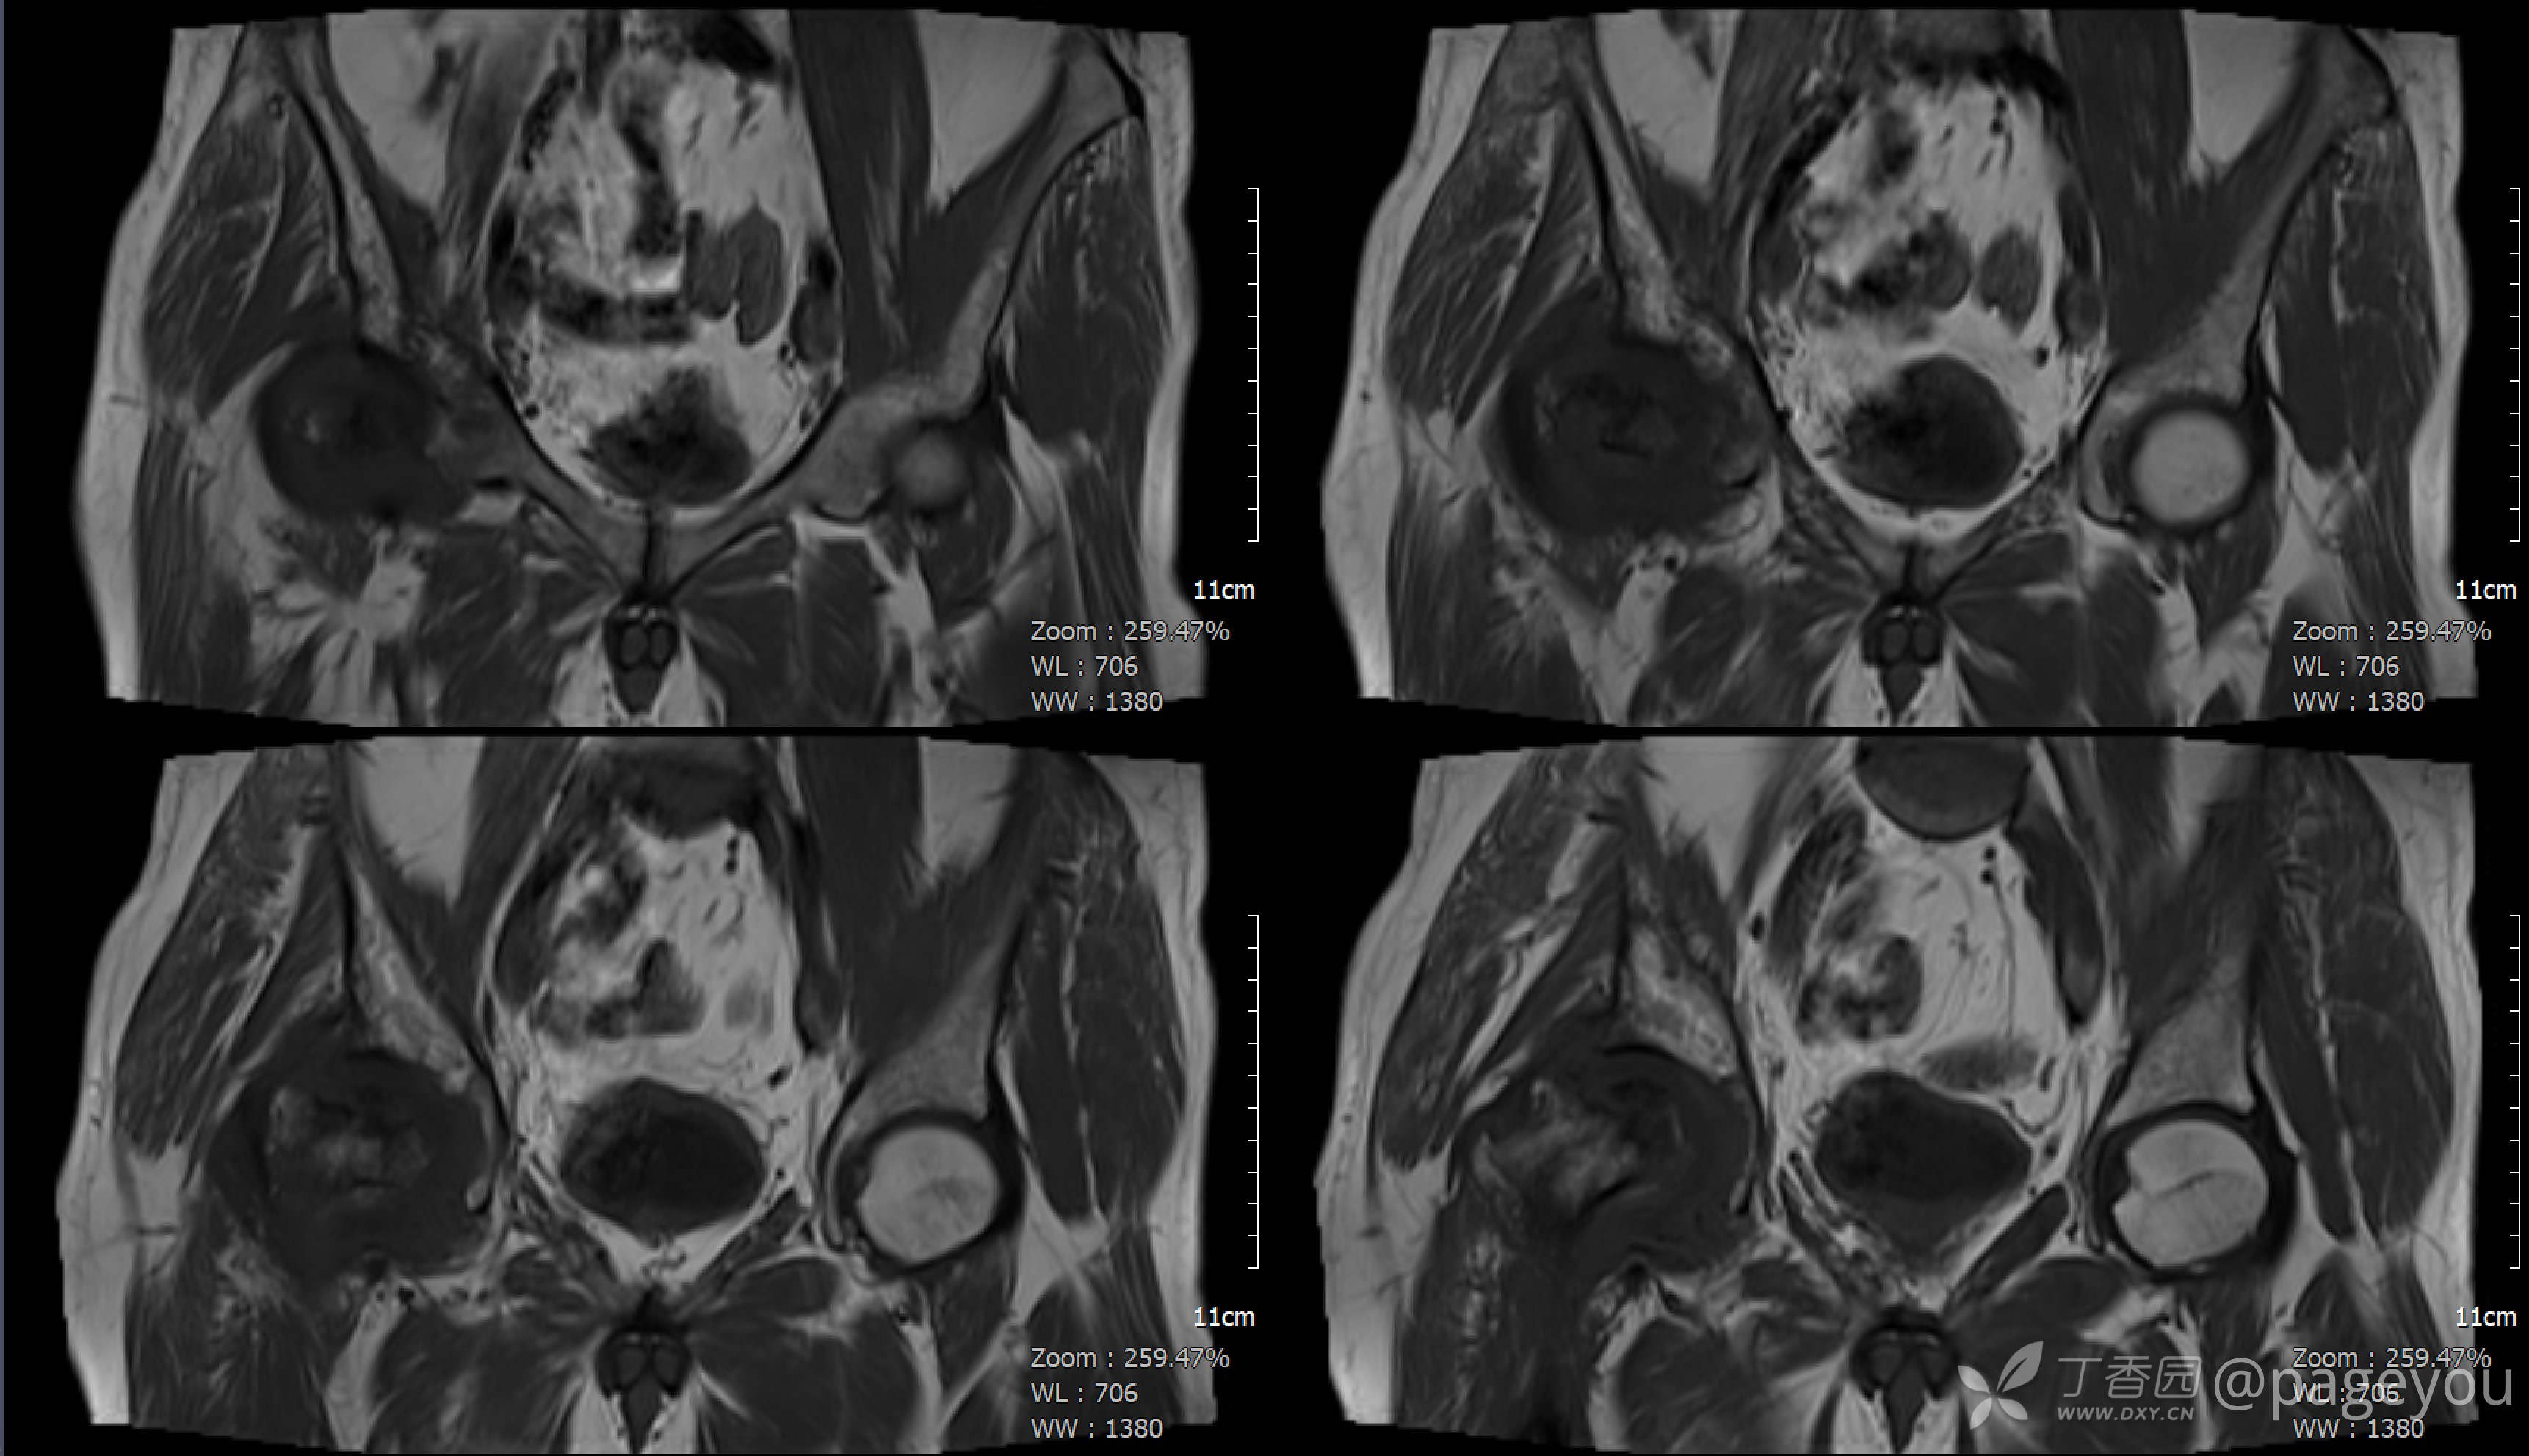

查骨盆MRI: